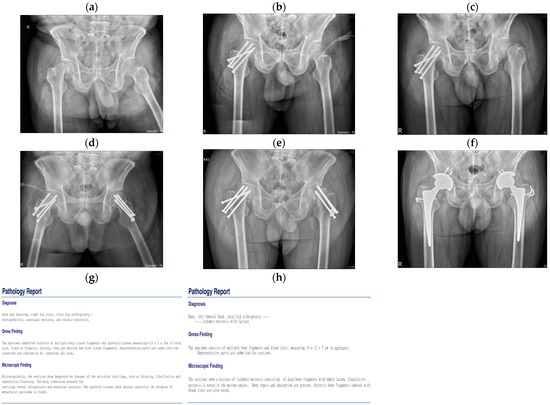

| Case | Age | Gender | Underlying | Risk Factors | Fracture Site | Trauma History | Diagnostic Tool | Surgical Treatment |

| No. 1 | 55 | Male | Hypertension | Alcoholic | Subcapital | No | X-ray | 1. Cannulated screws 2. THA |

| No. 2 | 52 | Female | Liver cirrhosis | Alcoholic | Subcapital | No | X-ray CT | 1. Bipolar 2. THA |